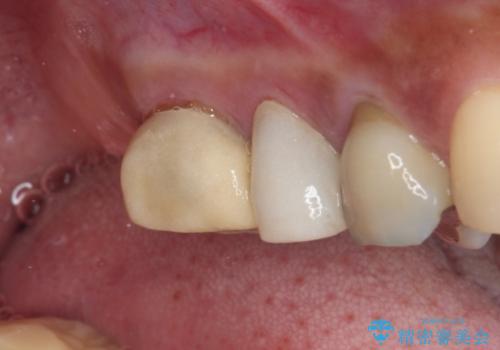

- 奥歯を治療しようと他院で開始したものの、放置してしまったとのことで来院された患者様です。

外れてしまった銀歯や穴の空いた仮歯などあり、適合の悪い被せものと合わせて、セラミッククラウンやセラミックインレーにて治療と行うこととしました。